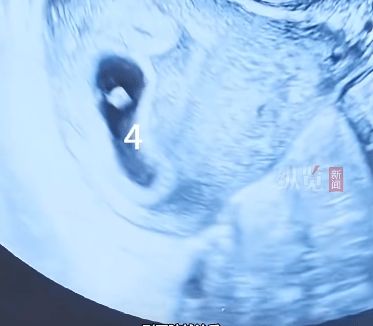

但早期产检显示竟是四胞胎

医生向李女士和家属释明:“保留四个胎儿,很可能一个都活不好。医学上,单胎或双胎妊娠对母婴最为安全。”医生实施了孕早期减胎手术,减灭其中两个胚胎,成功保留位置理想、发育良好的另外两个胚胎,手术过程顺利。